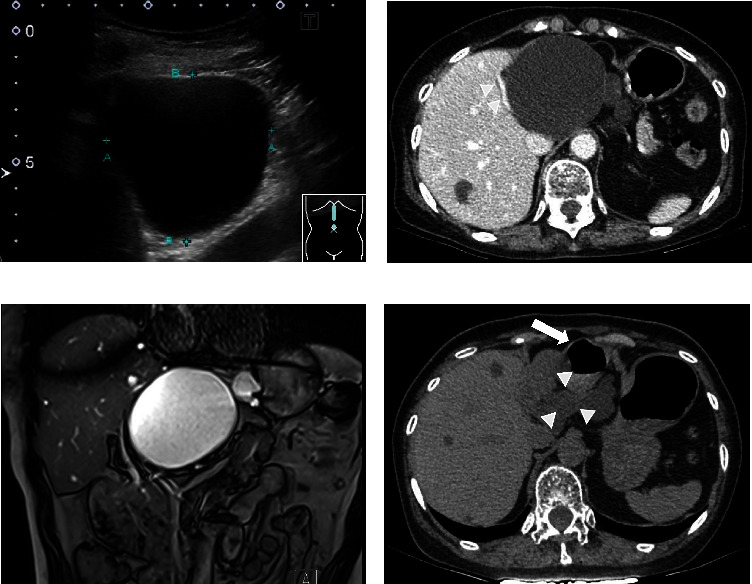

A liver cyst is hepatic fluid-filled cavities often detected in clinical surveillances such as a health examination. Although the liver cyst is usually asymptomatic and observed without any therapeutic intervention, it can be symptomatic and needs treatment due to its enlargement, hemorrhage, and infection. A 74-year-old woman presented with upper abdominal pain and a huge liver cyst in the left lobe. Several examinations including image findings revealed that the symptom could be derived from the liver cyst. Although there is no definite guideline of treatment for symptomatic liver cysts, percutaneous ultrasound-guided drainage with sclerotherapy or surgery is often selected. Because of anatomical accessibility to the liver cyst and the patient's wish, we performed endoscopic transgastric drainage with insertion of both an internal stent and an external nasocystic tube. Sclerotherapy with minocycline hydrochloride was performed through the nasocystic tube, and the liver cyst shrunk completely without any complications. This is the first reported method of administering minocycline hydrochloride through a nasocystic tube, which can be a therapeutic option for patients with symptomatic liver cysts.

Abstract Image